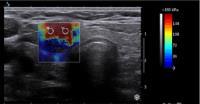

یکی از روشهای تشخیص سرطان پستان

سونوگرافی است، اما این روش تصویربرداری نمیتواند به هیچ عنوان جایگزین ماموگرافی

شود. ماموگرافی که سالانه در یک کلینیک معتبر مانند کلینیک تصویربرداری دکتر وهابآقایی انجام میشود بی شک یکی از راههای تشخیص سرطان به صورت دقیق و صحیح است.

سونوگرافی به تنهایی یک روش تشخیصی کامل برای سرطان سینه نیست،

زیرا از طریق آن فقط میتوان برخی از سرطانهای پستان را تشخیص داد. در واقع از

طریق ماموگرافی میتوان تعداد زیادی از کلسیفیکاسیونها را که در سونوگرافی قابل

مشاهده نیستند، تشخیص داد.

بسیاری از یافتههایی که در سونوگرافی مشکوک تشخیص داده میشوند و برای آنها نمونه برداری در

خواست میشود، در واقع تودههای بدخیمی نیستند. با توجه به اهمیت موضوع بهتر است و